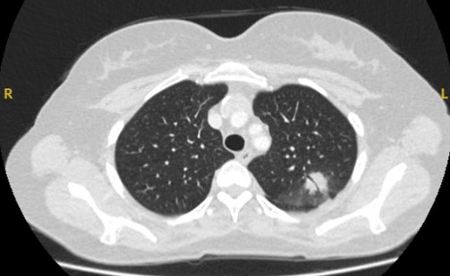

PET scanning can have a role in staging of tumours and has an especially high negative predictive value in excluding mediastinal involvement.[43][Figure caption and citation for the preceding image starts]: Computed tomography (CT) sections from two cases with benign perifissural nodules. Note the smooth margins and the normal undisturbed adjacent fissureFrom the collection of Dr George Tsaknis, MD, PhD, FRCP(London), MRQA, MAcadMEd, PGCert; used with permission [Citation ends].

[Figure caption and citation for the preceding image starts]: PET CT scan with 18-fluorodeoxyglucose (18-FDG) showing a low uptake in a semi-solid right upper lobe posterior lesion. Surgical resection confirmed adenocarcinoma with primarily lepidic patternFrom the collection of Dr George Tsaknis, MD, PhD, FRCP(London), MRQA, MAcadMEd, PGCert; used with permission [Citation ends].